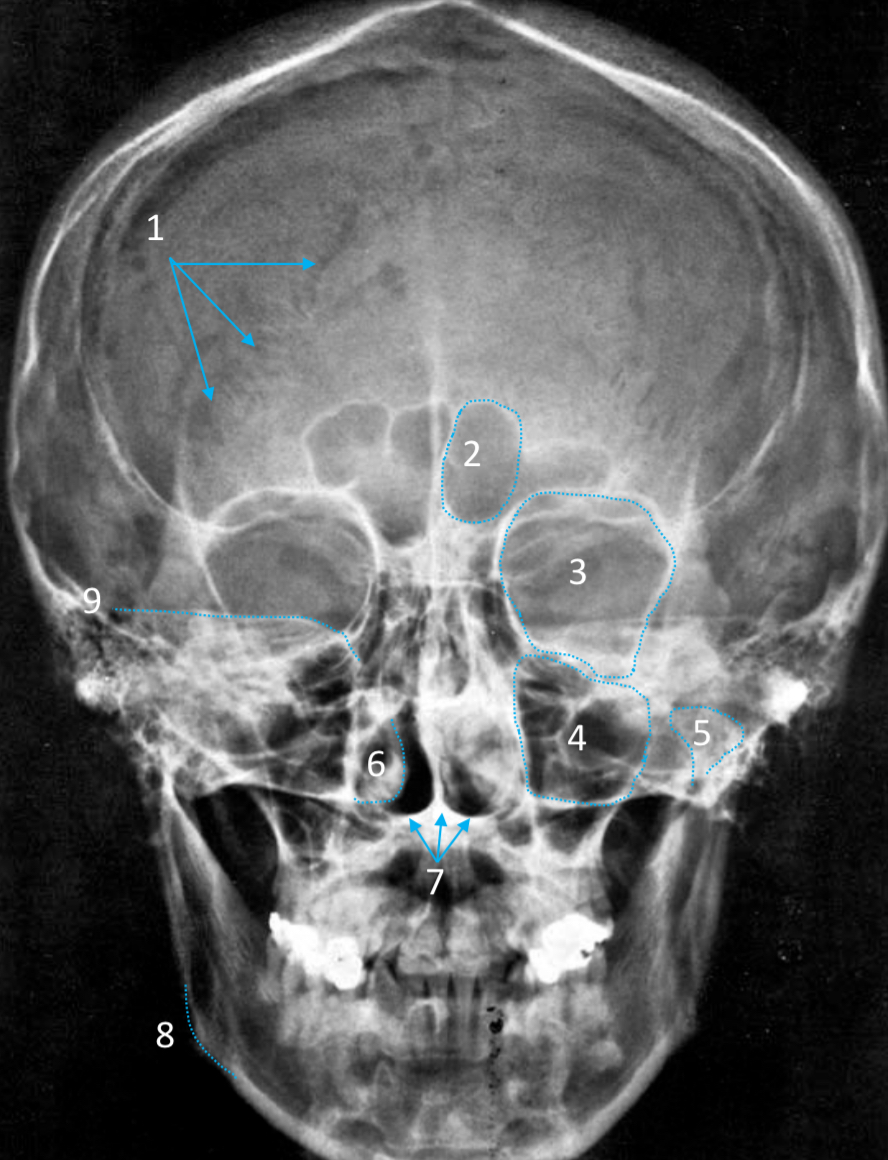

Frontal sinus

ID structure

Pituitary fossa

ID structure

Frontal sinus

ID structure

Orbital margin

Orbit

Maxillary sinus

ID structure

Mandibular condyle

ID structure

Inferior nasal concha

ID structure

Hard palate

ID strucutre

Gonial angle

ID strucutre

Petrous ridge

ID structure

Groove of middle meningeal a.

ID structure

Roof of orbit

ID structure

Frontal sinus

ID structure

Pituitary fossa

ID structure

Petrous ridge

ID structure

Sphenoid sinus

ID structure

Hard palate

ID structure

Mastoid air cells

ID structure

Zygomatic arch

ID structure

Mandibular condyle

ID structure

External auditory meatus

ID structure

Mastoid air cells

ID structure

Foramen magnum

ID structure

Foramen ovale

ID structure

Foramen spinosum

ID structure